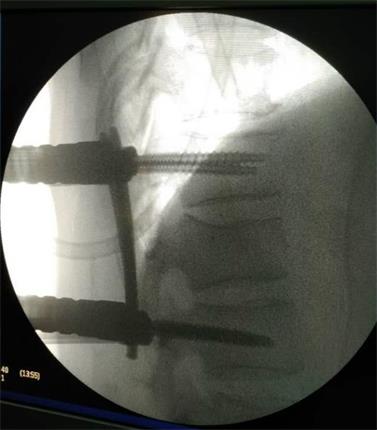

在成功的完成手術(shù)之后,使用過(guò)國(guó)內(nèi)外眾多品牌微創(chuàng)系統(tǒng)的主刀醫(yī)生對(duì)該P(yáng)INE III也給出了這樣的評(píng)價(jià):“操作真的方便太多,而且對(duì)壓縮骨折的復(fù)位效果也遠(yuǎn)超同類產(chǎn)品,以后就用這個(gè)了!”

該系統(tǒng)是針對(duì)胸腰椎后路微創(chuàng)手術(shù)設(shè)計(jì)的經(jīng)皮內(nèi)固定系統(tǒng),采用“自通道”設(shè)計(jì),置釘時(shí)無(wú)需釘尾延長(zhǎng)裝置,簡(jiǎn)化了微創(chuàng)手術(shù)經(jīng)皮固定的操作步驟,顯著地縮短了手術(shù)時(shí)間。同時(shí),超長(zhǎng)的釘尾設(shè)計(jì),超重患者不再是顧慮,適用范圍更廣!